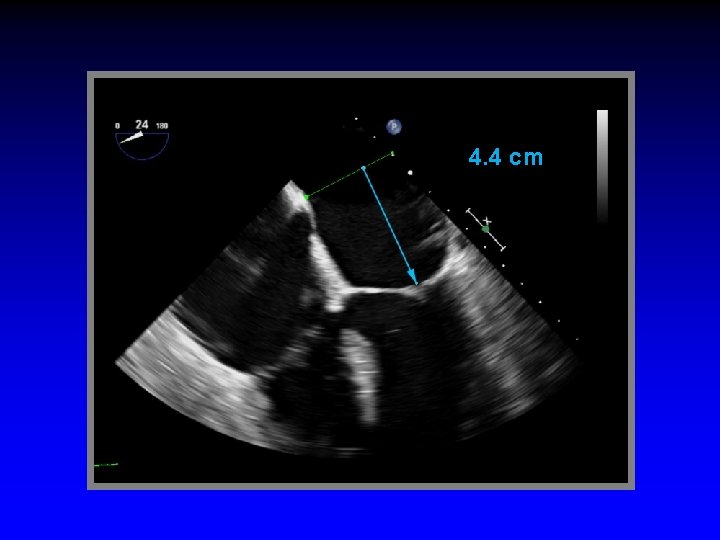

4. 4 cm